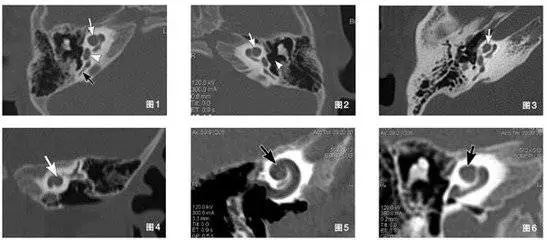

图1-6显示患者双侧耳蜗mondini畸形

多排螺旋CT主要观察内耳结构(骨迷路结构)。耳蜗畸形中,除Michel畸形、耳蜗未发育为手术的绝对禁忌症,其他类型内耳畸形均非人工耳蜗植入的禁忌症。不同内耳畸形术后可能出现不同的并发症,多层螺旋CT及其后处理技术,能从不同角度、由二维到三维立体显示内耳结构的大体形态,对不同畸形做出细致的分类,能帮助临床医生更好地预测手术中可能遇到的问题,合理地选手术方式和判断预后,有很高的应用价值。